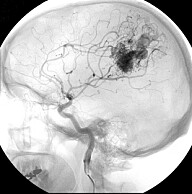

Arteriovenous malformation (AVM) in the brain

Det vanligste er et hjerneinfarkt på grunn av en blodpropp i hjernen. Den andre tilstanden er hjerneblødning.

Ved blodproppfisking går man inn i lysken med en bøyelig wire. Derfra føres den opp i hjernen hvor proppen hentes ut.